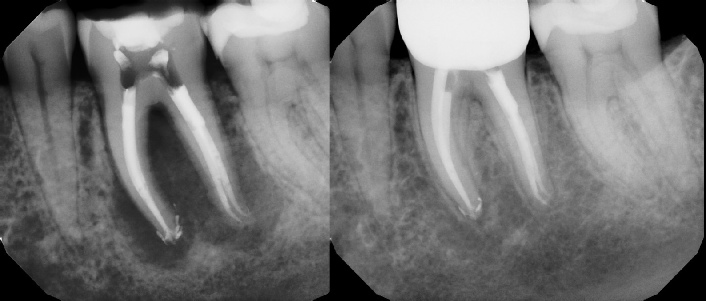

COMPLICATED ANATOMY LARGE LESIONS CALCIFIED CANALS PERFORATION / RESORPTION SEPARATED INSTRUMENTS SURGICAL CASES RETREATMENT / pOST REMOVAL OPEN APICES ACCESS THRU CROWNS Root Canal Case Portfolio

Pre-op Post-op 6 mos.